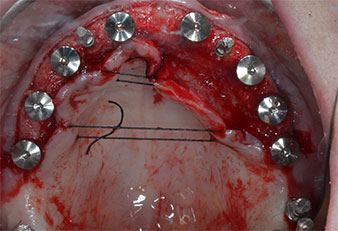

Debido al hueso relativamente duro (D2) existente en el sector anterior, los sitios de los implantes largos de 10 mm de las posiciones 11 y 21 se finalizaron con una fresa rotatoria de 4 mm de diámetro, en combinación con un contra-ángulo quirúrgico WS-75 L de W&H, el motor de implantes Implantmed de W&H y el módulo opcional Osstell ISQ de W&H. En cambio, debido a la existencia de hueso blando, los sitios posteriores se prepararon hasta un diámetro final de 3 mm utilizando el inserto Piezomed I3P. Por último, los implantes se colocaron a nivel crestal para su osteointegración durante tres meses (figuras 6-10). La prótesis existente se mantuvo sobre cuatro implantes provisionales (figura 8).

Implante en el nivel de tejido de 10 mm

Fig. 6: En la posición 21 se colocó un implante en el nivel de tejido de 10 mm. El implante de la posición 11 y los tres implantes posteriores izquierdos de 4 mm ya estaban colocados en su lugar.

Estabilidad del implante

Fig. 7: La estabilidad del implante se determinó con un SmartPeg y el módulo Osstell ISQ de W&H. Todos los valores se encontraron en un rango de medio a alto, con un ISQ mínimo de 69.

Implantes provisionales

Fig. 8: Después de la fijación de los formadores de encía, se colocaron implantes provisionales en las posiciones 18, 12, 22 y 28.